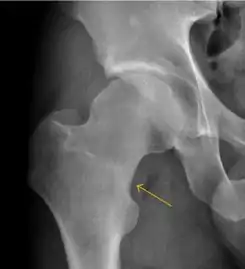

Plain radiography allows us to categorize the hip as normal or dysplastic or with impingement signs (pincer, cam, or a combination of both). Besides these, pathologic processes like osteoarthritis, inflammatory diseases, infection, or tumors can also be identified (Figure 1).[1]

Figure 1.

Radiography in normal hip

X-ray in pincer impingement type of hip dysplasia

X-ray of cam

Hip in osteoarthritis

Septic arthritis

- Slipped capital femoral epiphyses (SCFE)

Slipped capital femoral epiphyses (SCFE) usually affect 11- to 14-year-old adolescents (Figure 4). Radiographs may show widening and irregularity of the physis and posterior inferior displacement of the capital femoral epiphysis. On the AP view Klein’s line, tangent to the lateral aspect of the femoral neck, does not intersect the femoral head indicating that it is displaced. SCFE may compromise the blood supply to the femoral head and cause avascular necrosis, mainly when there is instability between the fragments.[1]

Figure 4: (a) X-ray of a 10-year-old child with left hip pain. It was considered normal at emergency despite the widening of the left physis (arrow). Two weeks later epiphysiolysis was evident (b). Despite appropriate surgical reduction (c) osteonecrosis developed and femoral head collapsed 1 month later (d).[1]